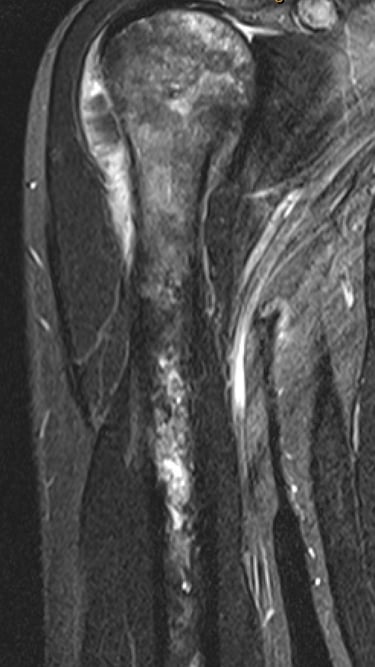

Osteosarcoma is the most common between the ages of 10 to 30 and those > 60 years old. There is no known cause in majority of patients but certain factors are known to increase your risk eg. previous radiotherapy, paget's disease, fibrous dysplasia, bone infarcts or Li Fraumeni syndrome. Most occur around the knee but can occur in any bone. Treatment generally involves combination of chemotherapy and surgery.

Diagnosis of this is generally made with Xrays, CT, MRI, PET scans and a core needle biopsy.